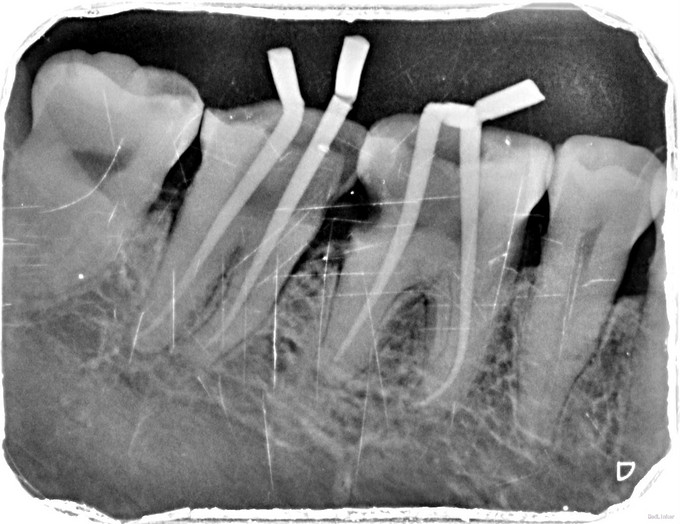

临床检查:46,47邻面龋坏,探(+),冷(++),叩(-),松动度(-),牙周正常. 35,36残冠,15,16,25缺失。 辅助检查:X线示46,47龋坏累积髓腔,36龋坏深达根分叉处。

诊断:46,47牙髓炎,35,36残冠。 治疗:经患者知情同意后,46,47局麻去腐降牙合,开髓拔髓寻找根管口,建立直线通路,扩通根管,确定工作长度。S3/EDTA凝胶镍钛器械,低浓度次氯酸钠冲洗根管,预备至35/04,氢氧化钙诊间封药,患者符合拔牙适应症,拔除35,36.一周后复诊,试主尖X线示恰充,试干根管,导AH-PLUS糊剂,VDW热压胶垂直加压根充,术后见根管恰充,暂封调合抛光。观察一周桩冠修复。